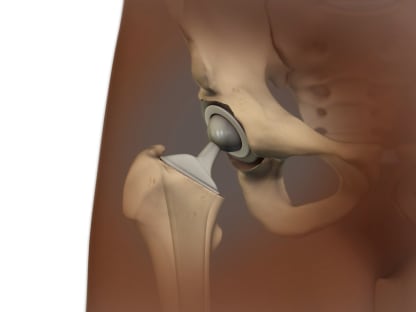

- Joint replacement.

This is done when other treatments haven't worked and damage to the joint can be seen on X-rays. It involves surgery to replace the ends of bones in a damaged joint. The surgery creates new joint surfaces. The joints that are replaced most often are the hip, knee, and shoulder. But other joints such as the elbow and the ankle can also be replaced.